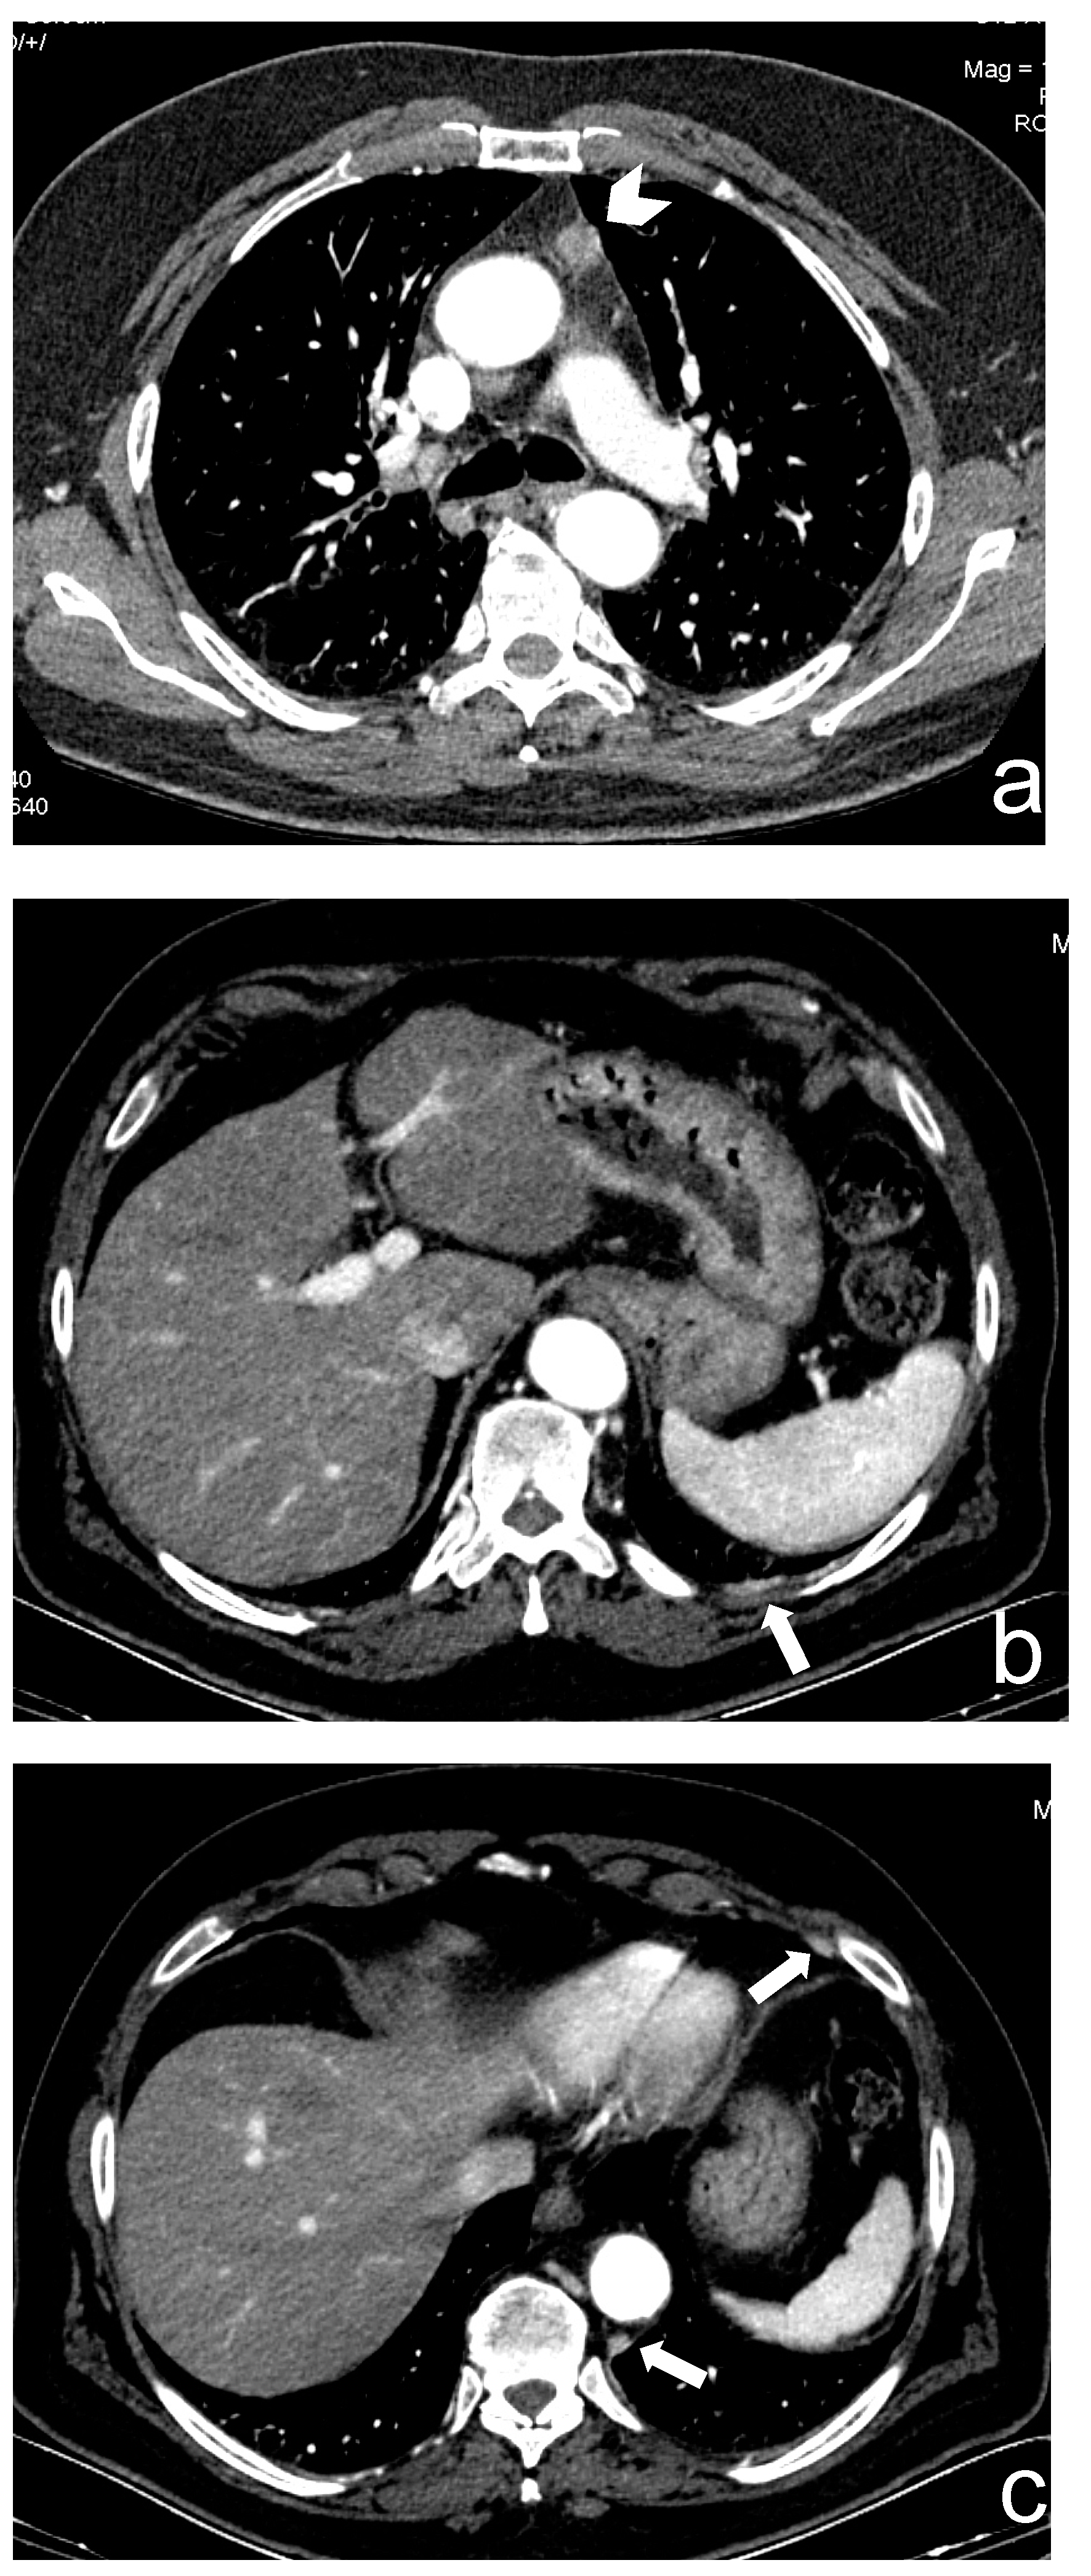

Chest CT is the first imaging modality performed for a clinical or X-ray suspicion of a thymic lesion, thanks to its low-cost, wide availability and fast execution. The exam should include a scan without contrast medium and a post-contrast scan in late arterial phase, from diaphragmatic pillars to the base of the neck, in order to evaluate the presence of ectopic lesions and pleural, diaphragmatic metastases [5,6,7,8,9,10] (Figure 1).

Figure 1.

(a–c) A 66-year-old man who underwent robotic surgery in March 2016 for a thymic basaloid carcinoma (stage I, arrowhead in (a)). In June 2020, small bilateral pleural metastatic lesions appeared without pleural effusion (arrows in (b,c)).